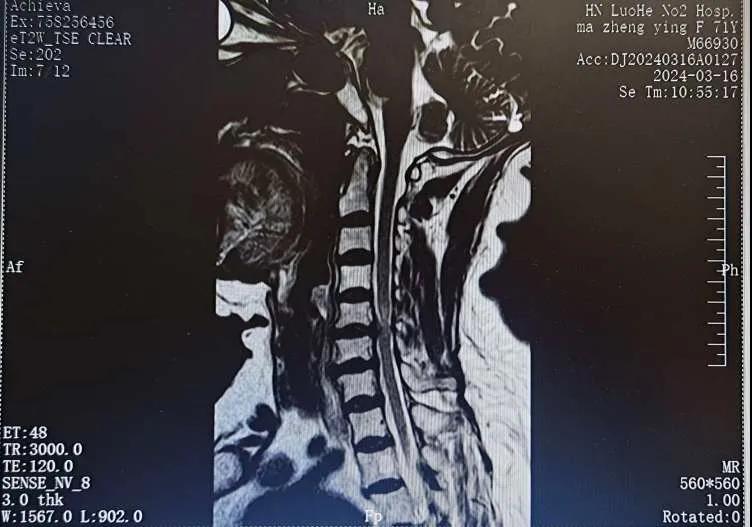

近日,70歲的馬阿姨,因摔傷后出現持續性頸部疼痛伴右側肢體無力、麻痛,影響日常生活。于是來到市二院神經外科就診,經檢查發現:頸椎MR示:頸3/4、4/5、5/6、6/7椎間盤變性突出(中央型)并繼發性椎管變窄,頸椎退行性改變,頸5椎體水平頸髓水腫。神經外科副主任劉沛濤根據患者癥狀、體征、影像學三者結合診斷為“脊髓型頸椎病”,考慮到患者癥狀逐漸加重、保守治療效果不佳等情況,建議盡快手術治療。